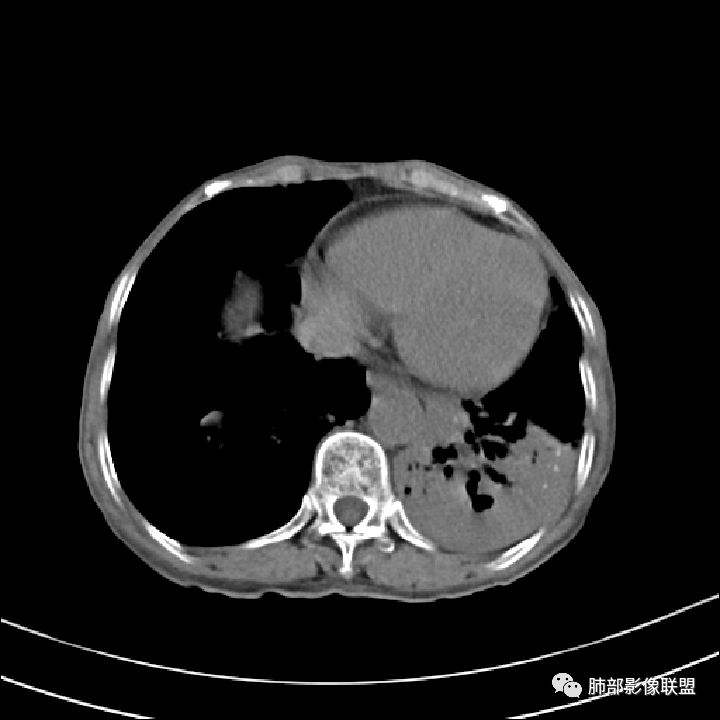

这些应该是胸水

支气管扩张、扭曲成团,附近钙化灶

纵膈也左移了

这例左下叶的体积是整体缩小的,左下叶的支气管主干稍微小一点点,然后左上叶的下舌段也有类似的病灶,然后我们看到一团乱的支气管扩张,但它有特点,边缘凹凸不平。那什么样的支气管扩张边缘会如此凹凸不平呢,等我截个图:

首先这幅图支气管很多地方是扭曲的,远端扩张的特别厉害。如果是肿瘤,首先考虑淋巴瘤,因为支气管可直达远端,稍扩张,但是它的前提是周围要实性占位的,而且它不会这样扭曲变形。我们看这个病例的支气管扩张,它支气管扩张占大部分区域,中间稍有些实性的结构,这就不符合了。这幅图你会发现所有支气管都是扩张的,实性部分偏少,外围胸水。所以我更倾向慢性炎性病变,能够引起支气管扩张的炎性病变有哪些?结核?NTM?支扩伴感染?大方向是慢性炎性病变。这些左下肺播散出来的病灶,咳中等量黄浓痰,我考虑还可能合并细菌感染。

2.左肺下叶大范围病灶,其间柱状支气管扩张相当显眼。